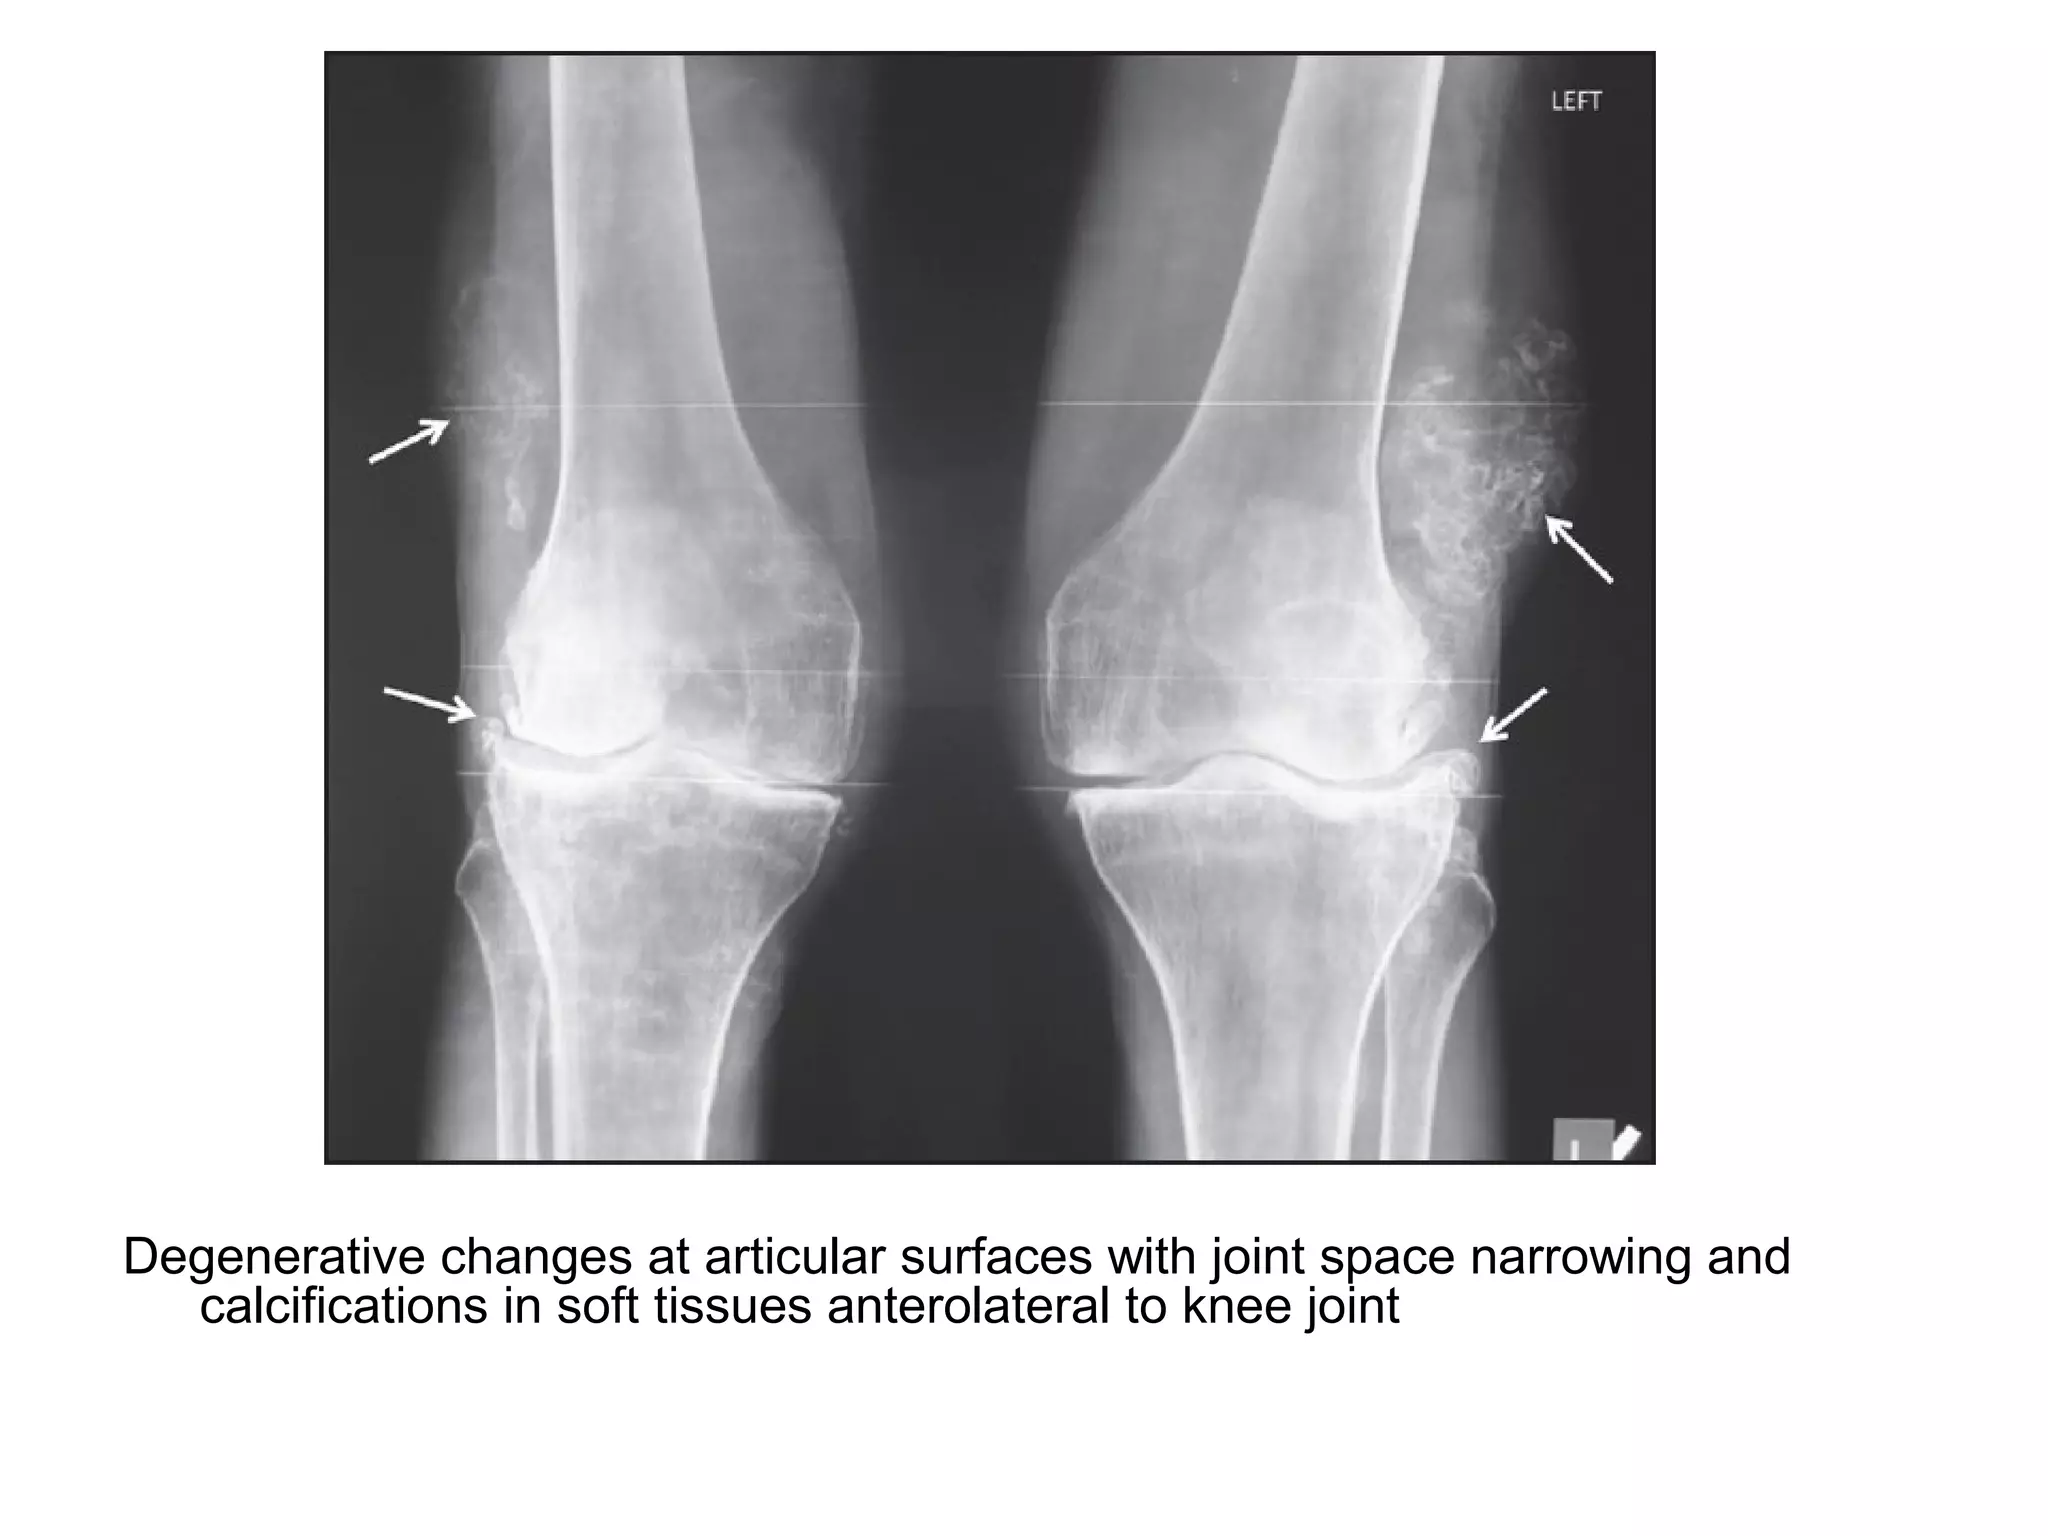

Degenerative changes at articular surfaces with joint space narrowing and

calcifications in soft tissues anterolateral to knee joint

Shoulder joints showing degenerative changes